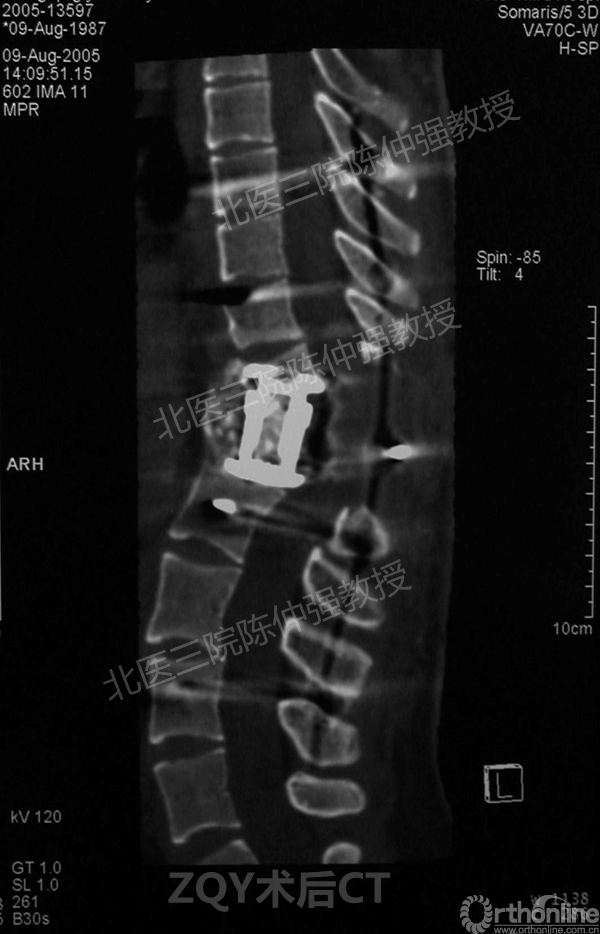

陈仲强教授病例分享

2005年,陈仲强教授在AOSpine年会上分享了一例胸腰椎陈旧结核性侧后凸畸形病例。资料如下:

ZQY术后

患者女性17岁,胸腰椎陈旧结核性侧后凸畸形,局部呈“麻花状”扭转,无神经功能受损表现。2005年,陈仲强教授带领团队实施后路+侧前方联合入路脊柱节段切除、双轴旋转矫形术。术后患者外观显著改善,神经功能正常。术后随访证实患者截骨矫形节段骨性融合良好,矫形效果持续良好。